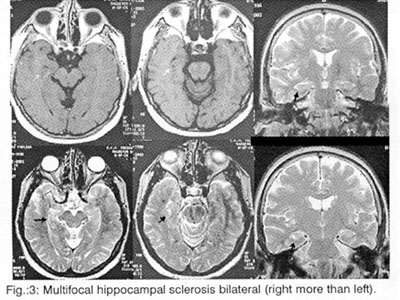

But the most important task of the Neuroimaging is (always in connection to the clinic) the help to the localisation of the lesions (which provoke the epileptic seizures), to the differential diagnosis of this lesion among hereditary illnesses (phacomatoses, leukodystrophies), abnormalities of development (dysplasias, vascular malformations, neuronal migration disorders: heterotopia-double cortex syndrome (Fig. 1), schizencephaly, lissencephaly, unilateral Megalencephaly), perinatal cerebral injuries (between the 30th week of pregnancy and the end of the first month of life due to placental insufficiency, hypoxia, infections, intoxication and mechanical birth trauma4, presented as porencephaly, focal or generalized enlargement of the ventricular system or the subarachnoid space (Fig. 2), hippocampal sclerosis (Fig. 3 and 4) or acquired lesions (benign or malign neoplasms, cerebrovascular diseases, encephalitis (Fig. 5), cerebral abscess, parasitic, fungal and protozoan diseases (Fig. 6), cerebrocranial injuries, degenerative diseases), for the best coping with the patient's problem (conventional pharmaceutical or neurosurgical treatment), as well as for the prognosis before and after the preferred therapy.